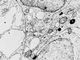

Клетки щитовидной железы крысы с включениями (увеличено в 18000 раз). Условные обозначения: 1 — ядро, 2 — ядерная оболочка, 3 — клеточная оболочка, 4 — эндоплазматическая сеть, 5 — митохондрии, 6 — комплекс Гольджи, 7 — плотные тела, 8 — рибосомы.